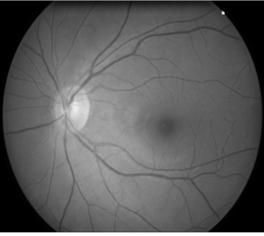

. The developed computer

system for retina non-invasive diagnostics of the visual analyzer makes it possible to carry out image capture, analysis

and measurement of the retina in real time (fig. 1). The specialized software

can realize the automatic mode of operation of computer theme, adaptation for

the conditions of control and observation, processing of video information and

measurement of integral informative parameters of images.

Figure 1 – Image of retina visual analyzer

physiological norm